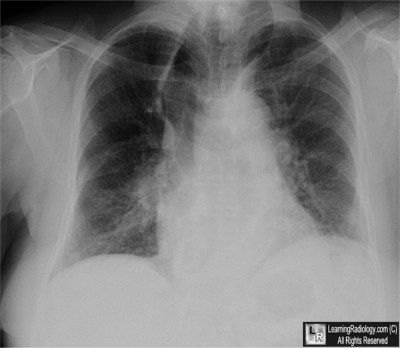

Frontal Radiograph of the Chest

- Achalasia